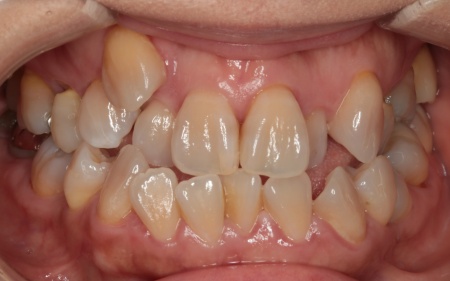

治療前

診断結果 拝見したところ、上下の歯がデコボコに乱れて生えていました。

歯の大きさに対して顎が小さいため、歯が正常に並びきらず、全体的な噛み合わせのバランスも崩れています。

噛み合わせを詳しく検査したところ、実際にしっかりと噛み合っているのは一部の歯だけで、このまま放置すると特定の歯に負担が集中し、将来的に痛みや違和感が生じるおそれがあります。

以上のことから、温存が難しい歯を抜いたうえで、矯正治療によって歯並びと噛み合わせを整える必要があると診断しました。